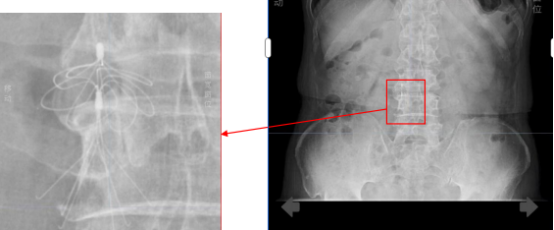

当时,因严重下肢静脉血栓,王大爷接受了下腔静脉滤器植入术,这枚金属滤器如同一张“血管防护网”,曾有效拦截血栓,守护了他的生命。可如今,它却成了房颤导管消融手术的“拦路虎”——该手术常规路径需经大腿股静脉,通过下腔静脉进入心脏,但滤器恰恰堵住了这条必经之路。若强行通过可能导致滤器移位、血管破裂或血栓脱落,风险极高。加上滤器植入时间过长,取出滤器的风险同样不亚于手术本身。

经过对影像资料反复推演,团队终于为王大爷量身定制了创新方案:经右侧颈内静脉入路,在三维超声引导下实施零射线房颤射频消融术。